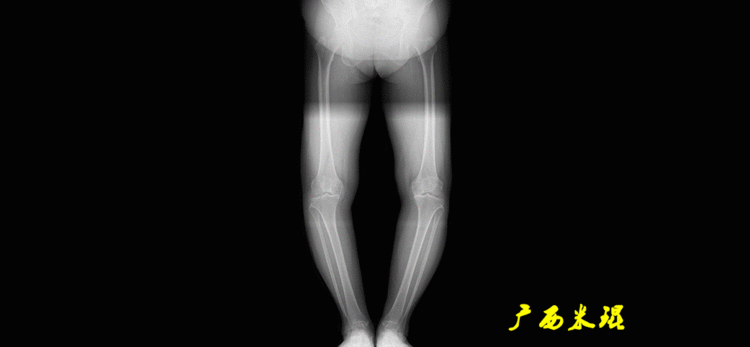

解剖胫骨近端外侧角(也叫aMPTA):胫骨干上段轴线与胫骨平台切线(关节线)在膝关节外侧所形成的夹角,常称为胫骨角,正常为87°±3°。大多数膝内翻患者的畸形发生于胫骨上端,表现为胫骨角大于90°。严重的膝内翻畸形发生在整个下肢,股骨干及胫骨干都有可能形成向内弯曲的弧形。

1、判定有无畸形下肢的畸形定义为生理轴线的偏移。关节角和轴线在冠状面、矢状面和横断面上可发生病理改变,并引起整个下肢的对线异常。

最常见的下肢畸形发生于冠状面,即膝内外翻畸形,冠状面的对线异常通过应用“对线异常检验”进行分析,机械轴的偏移(MAD)表现为对线异常。

膝内翻是指下肢力线通过膝关节中心点内侧,距中点2mm以上,偏内超过15mm为显著膝内翻。膝外翻是指下肢力线通过膝关节中心点外侧,距中点2mm以上,偏外超过10mm为显著膝外翻。